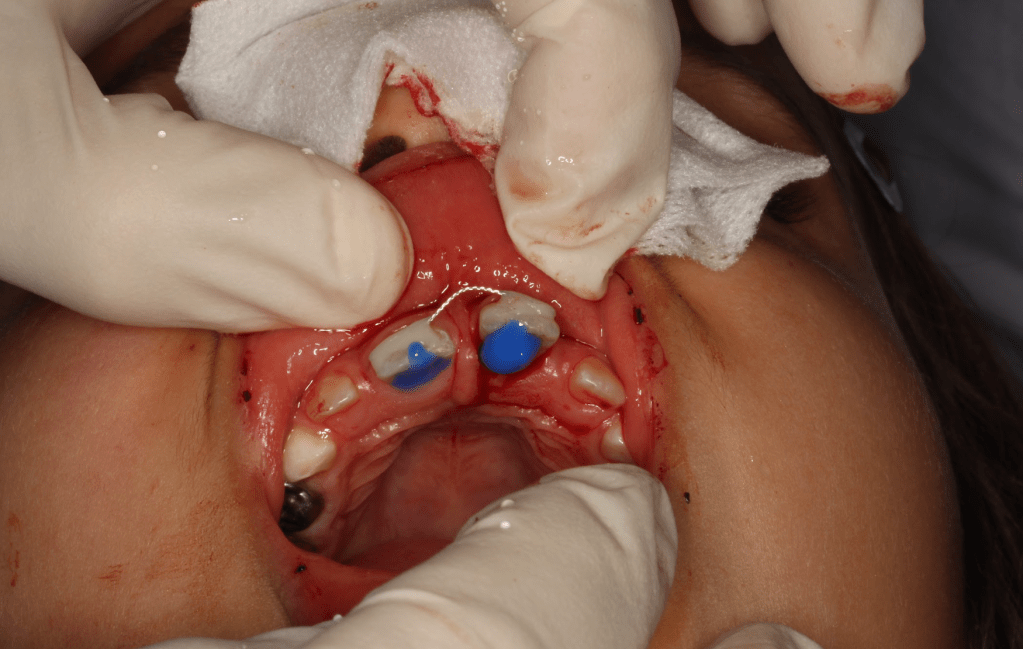

Gingivectomía + pulpotomía biodentine + reconstrucción

Reconstrucción preendodóntica

Reco pre-endo gingivectomái, pared yuxtaosea

Reco preendo + gingivectomía